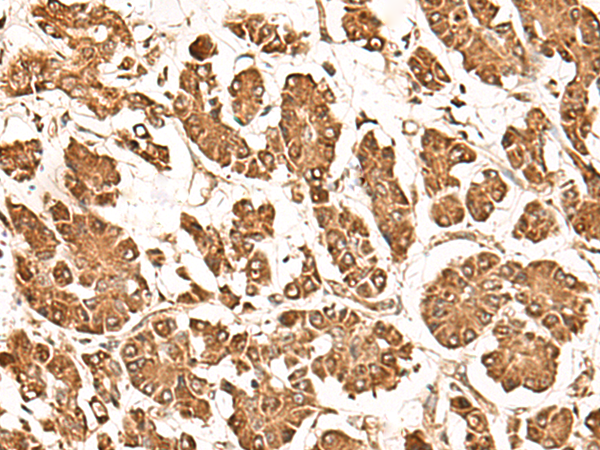

IHC positive control: |

Human gastric cancer and Human thyroid cancer |